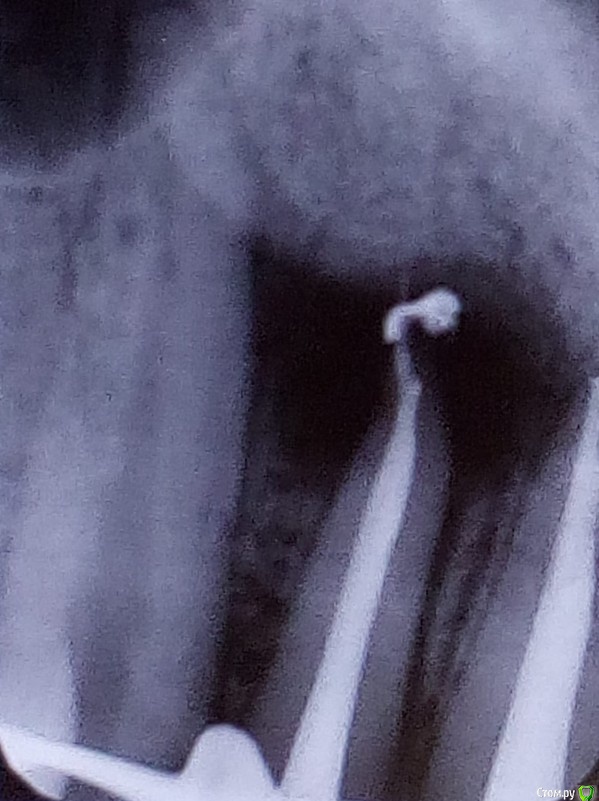

Shelly2000 Опубликовано 10 июля, 2017 Поделиться Опубликовано 10 июля, 2017 Уважаемые специалисты! Помогите, пожалуйста, понять, что изображено на снимках.Было лечение кисты зуба 12, потом пломбирование каналов 12 и 11, потом установлена вкладок в оба зуба.На первом контрольном снимке в момент пломбирования и на втором снимке в момент примерки вкладок около верхушки корня зуба 12 наблюдается нечто инородное.По яркости от пломбировочного материала отличается. Плюс видно перемещение относительно зуба и небольшое изменение формы. Разница по времени между снимками - чуть больше месяца.Что это может быть? Насколько опасно? Ссылка на комментарий

St. Опубликовано 10 июля, 2017 Поделиться Опубликовано 10 июля, 2017 Ничего критичного не увидела.скорее всего пломбирования материал. Наблюдайте. Через 6 и 12 мес нужно будет сделать контрольные снимки. Ссылка на комментарий

dok1 Опубликовано 11 июля, 2017 Поделиться Опубликовано 11 июля, 2017 Милионы людей ходят с подобными артефактами и ничего. Да, конечно, хочется идеальную картинку с пломбировочным материалом в пределах корня. Но современные материалы не раздражают ткани за пределами корня так, как это делают старые, отжившие своё цементы и пасты. А иногда выведение малого количества лечебной пасты заложено технологией лечения. Так что всё у вас в пределах нормы. 2 Ссылка на комментарий

AndyAndy Опубликовано 11 июля, 2017 Поделиться Опубликовано 11 июля, 2017 Я вижу значительное уменьшение воспалительного процесса на верхушке корня. Так что я бы на вашем месте радовался, и забил бы на выведенный материал Ссылка на комментарий